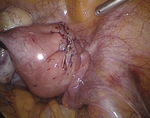

Po wytworzeniu odmy otrzewnej wprowadzono przez pępek trokar 10 mm, a następnie optykę laparoskopu i trokary dodatkowe w podbrzuszu 5 i 10 mm. Pacjentkę ułożono w pozycji Trendelenburga. Uwidoczniono powiększony trzon macicy, ścianę przednią uwypukloną przez mięśniak śródścienny o średnicy około 4-5 cm (ryc. 1), przydatki obustronnie bez zmian. Pozostałe narządy jamy otrzewnej dostępne wizualizacji laparoskopowej były niezmienione.